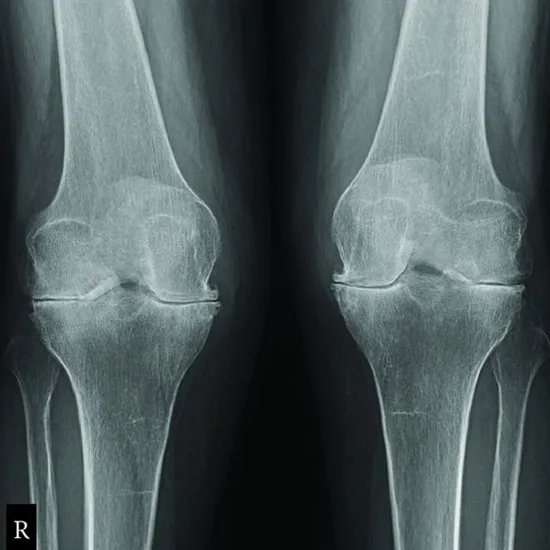

The knee joint can be seen on an X-ray of the knee test. With the knee bent 60 degrees, the tunnel view is a frontal view. It can be taken from the front (AP) with the patient lying down or from the back (PA) with the patient facing forward or kneeling on the cassette.

• To diagnose knee fractures and monitor healing following setting.

• For diagnosing infections, osteoporosis, deformities, or abnormal bone development.

• For diagnosing osteoarthritis or knee dislocation.